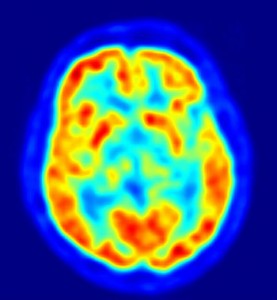

Os pesquisadores acompanharam a atividade cerebral das pessoas durante o teste por meio de ressonância magnética.

Eles acreditam que as partes do cérebro envolvidas nas previsões, quando estão com um funcionamento não adequado, podem causar problemas na memória e no ato de entender as coisas que se passam ao redor.